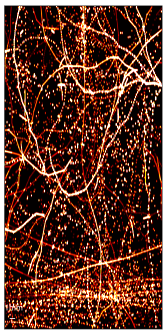

Figure 3: SR images of the test dataset, i.e., the last 100 frames of a simulation video from the challenge dataset obtained from (a) Ground Truth (b) DETR and (c) DE-DETR.

The mAP and mAR for DETR are: 80.12% and 55.17% and for DE-DETR they are: 87.60% and 63.79%. The super-resolution maps are generated using a proper Gaussian around each MB location and shown for comparison in Figure 3.